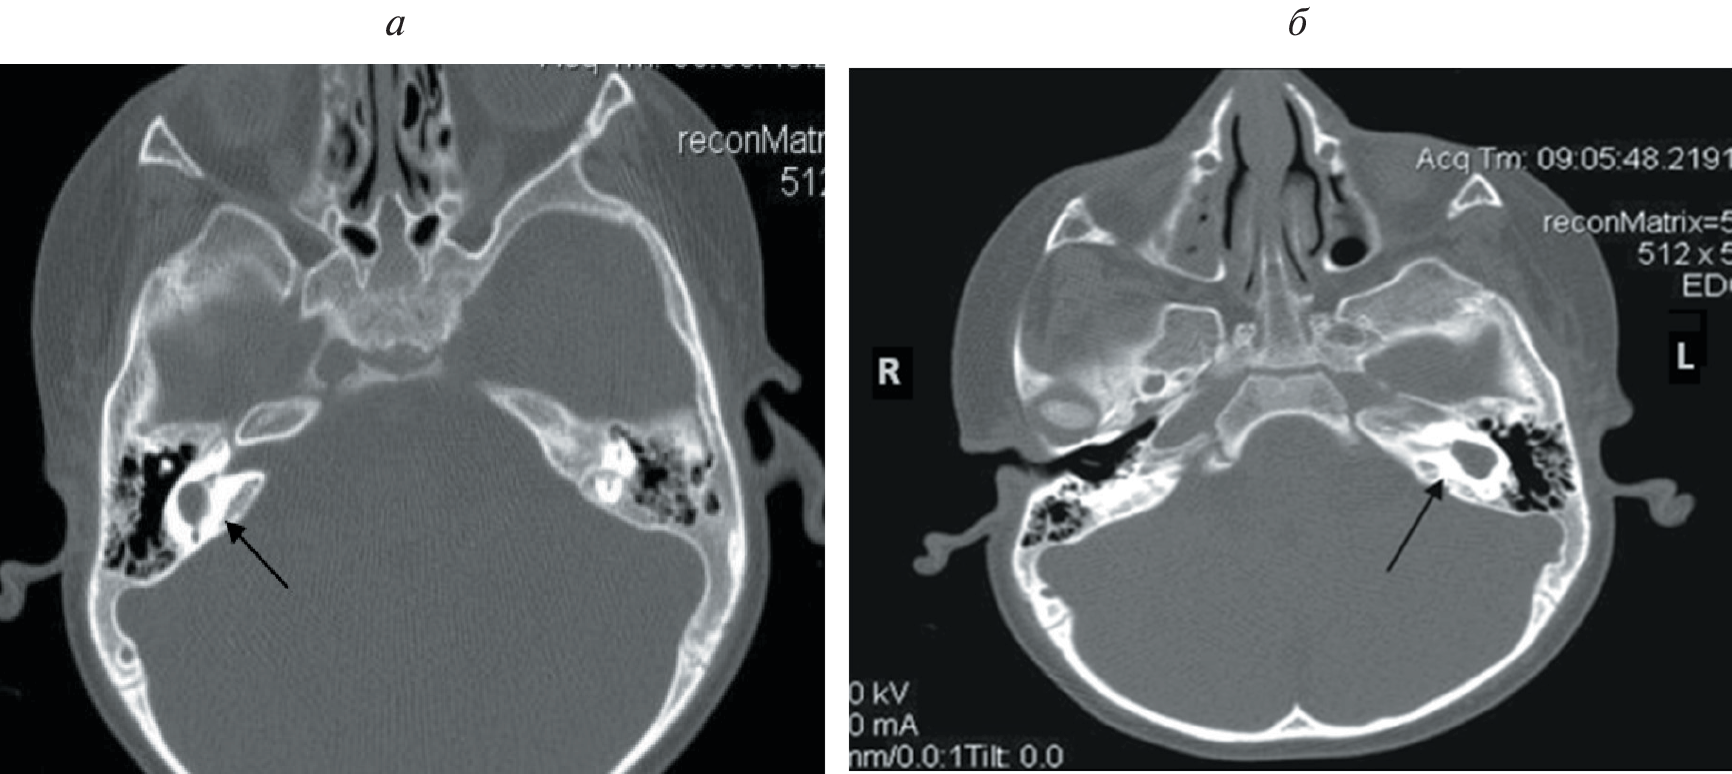

According to various authors, 20% of children with sensorineural hearing loss or deafness, anomalies in the structure of the temporal bones are determined according to the results of computed tomography. Cochlear implantation in the presence of cochleovestibular malformations is associated with a number of difficulties. These include the peculiarities of cochleostomy and placing of the electrode inside the cochlea, the risk of damage to the facial nerve due to its abnormal location, intraoperative liquorrhea, which can lead to the development of bacterial meningitis in the postoperative period, as well as the risk of penetration of the electrode into the internal auditory canal. In this research, we present our method of performing cochlear implantation in case of a malformation in the development of the inner ear (common cavity). The method expands the possibilities of cochlear implantation for e auditory perception in patients with this pathology.